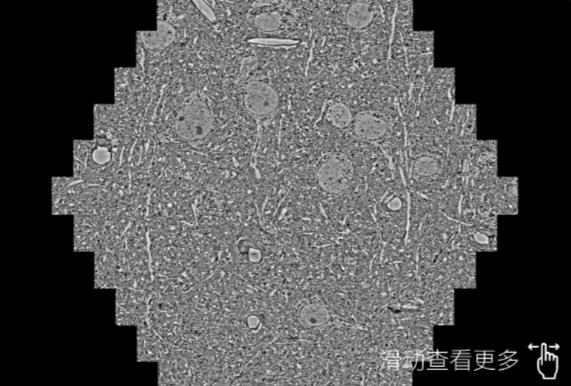

鼠脑切片。左图使用佳木斯蔡司佳木斯扫描电镜MultiSEM706对165μmx143pm面积区域成像,耗时仅需1.5秒。右图为鼠脑切片中30μm区域放大效果。样品由芝加哥大学B.Kasthuri提供。

使用蔡司高速佳木斯扫描电镜MultiSEM对1mm²人脑皮层组织进行高分辨成像,并对其中的各种细胞结构进行三维重构分析。左图展示了2x3mm²组织平面中锥体神经元的三维重构效果。右图显示了局部体积神经元三维重构。图像由哈佛大学chtman实验室提供,渲染图由D. Berger 制作。